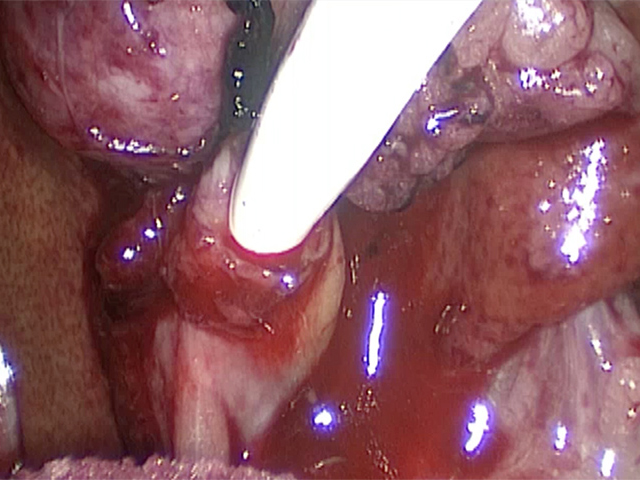

胆嚢の頸部に糸を通し動脈を確保しています。

総胆洗浄をして詰まりがないかまずは確認します。

きれいに開通していました。鉗子が大きく感じますが体が小さいので大きく見えます。